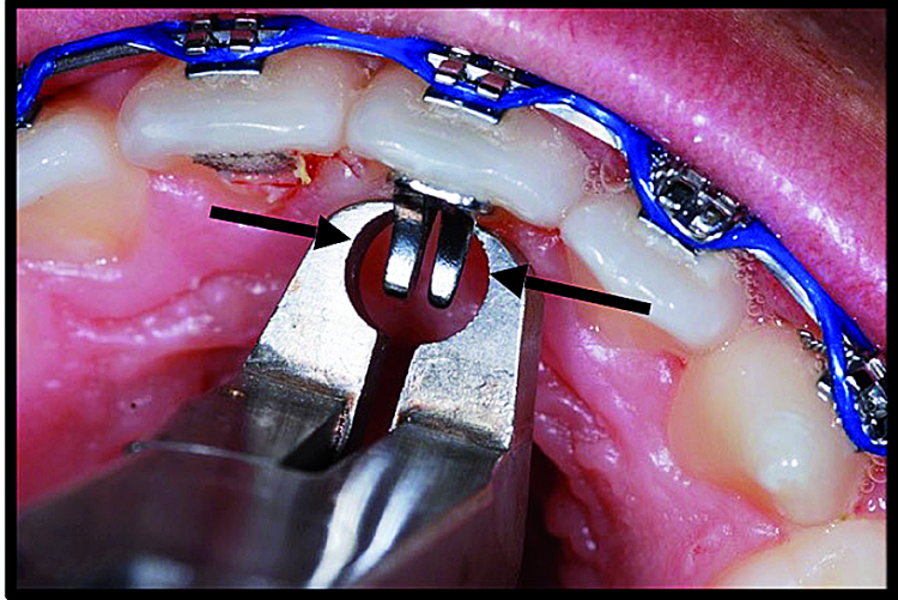

BiTurbo2 system for rapid deep overbite correction